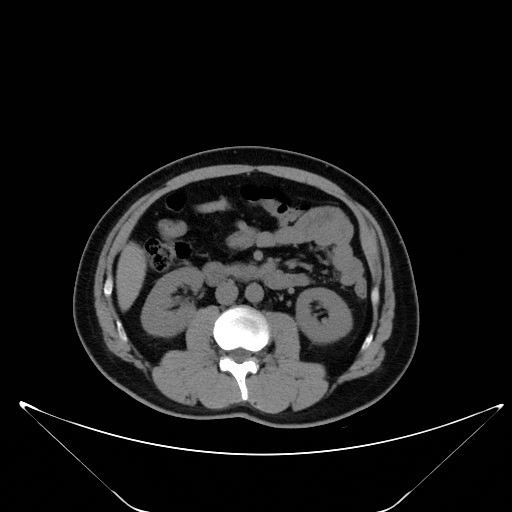

CT 有较高的密度分辨率,对脂肪组织的区分有显性作用。

①盆腔内部呈现大面积低密度阴影,CT 值-100 HU 左右,密度均匀或欠均匀,无明确边界,增强扫描无强化, 这是盆腔脂肪增多症的特征性表现。

②膀胱及周围脏器如直肠或子宫或前列腺及精囊腺均因受压表现出不同程度的变形、移位或上抬或前移。膀胱、直肠表现最为明显。